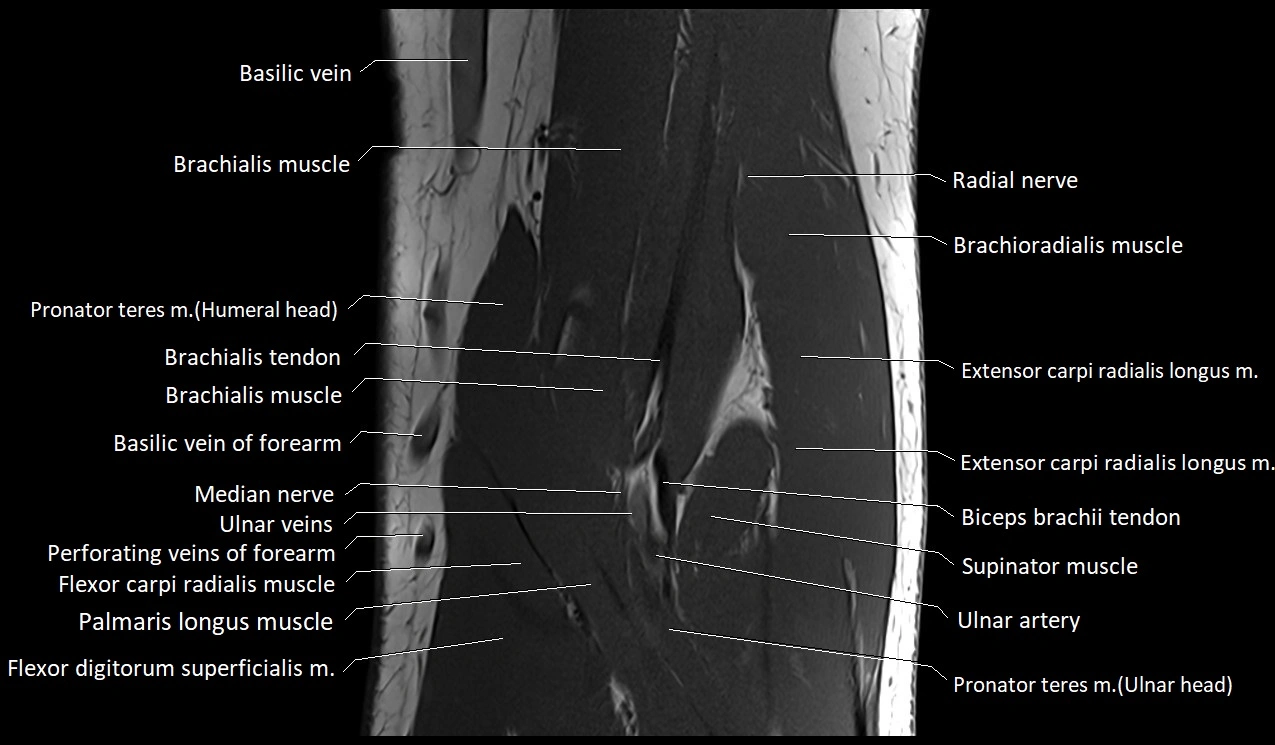

MRI image

image